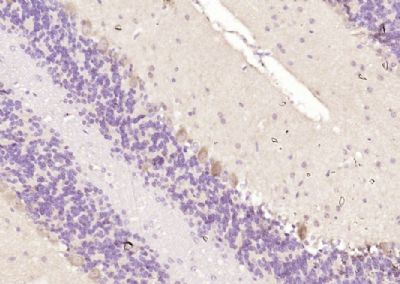

红细胞蛋白Ank1抗体

目录号:bs-7594R